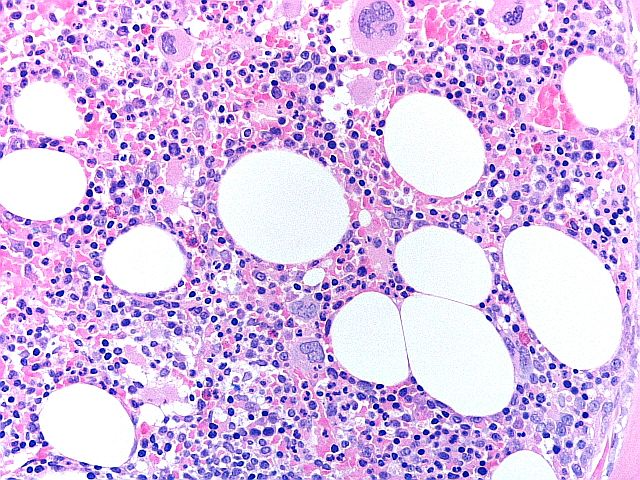

BMT Scheme

Narito ang isang slide mula sa BMT scheme. Ibinawas ang mga marka para sa paglamlam sa background at hindi tiyak na deposito ng pilak na nagtatakip sa pagpapakita ng mga hibla. Ang slide na ito ay nakakuha ng 5/10.